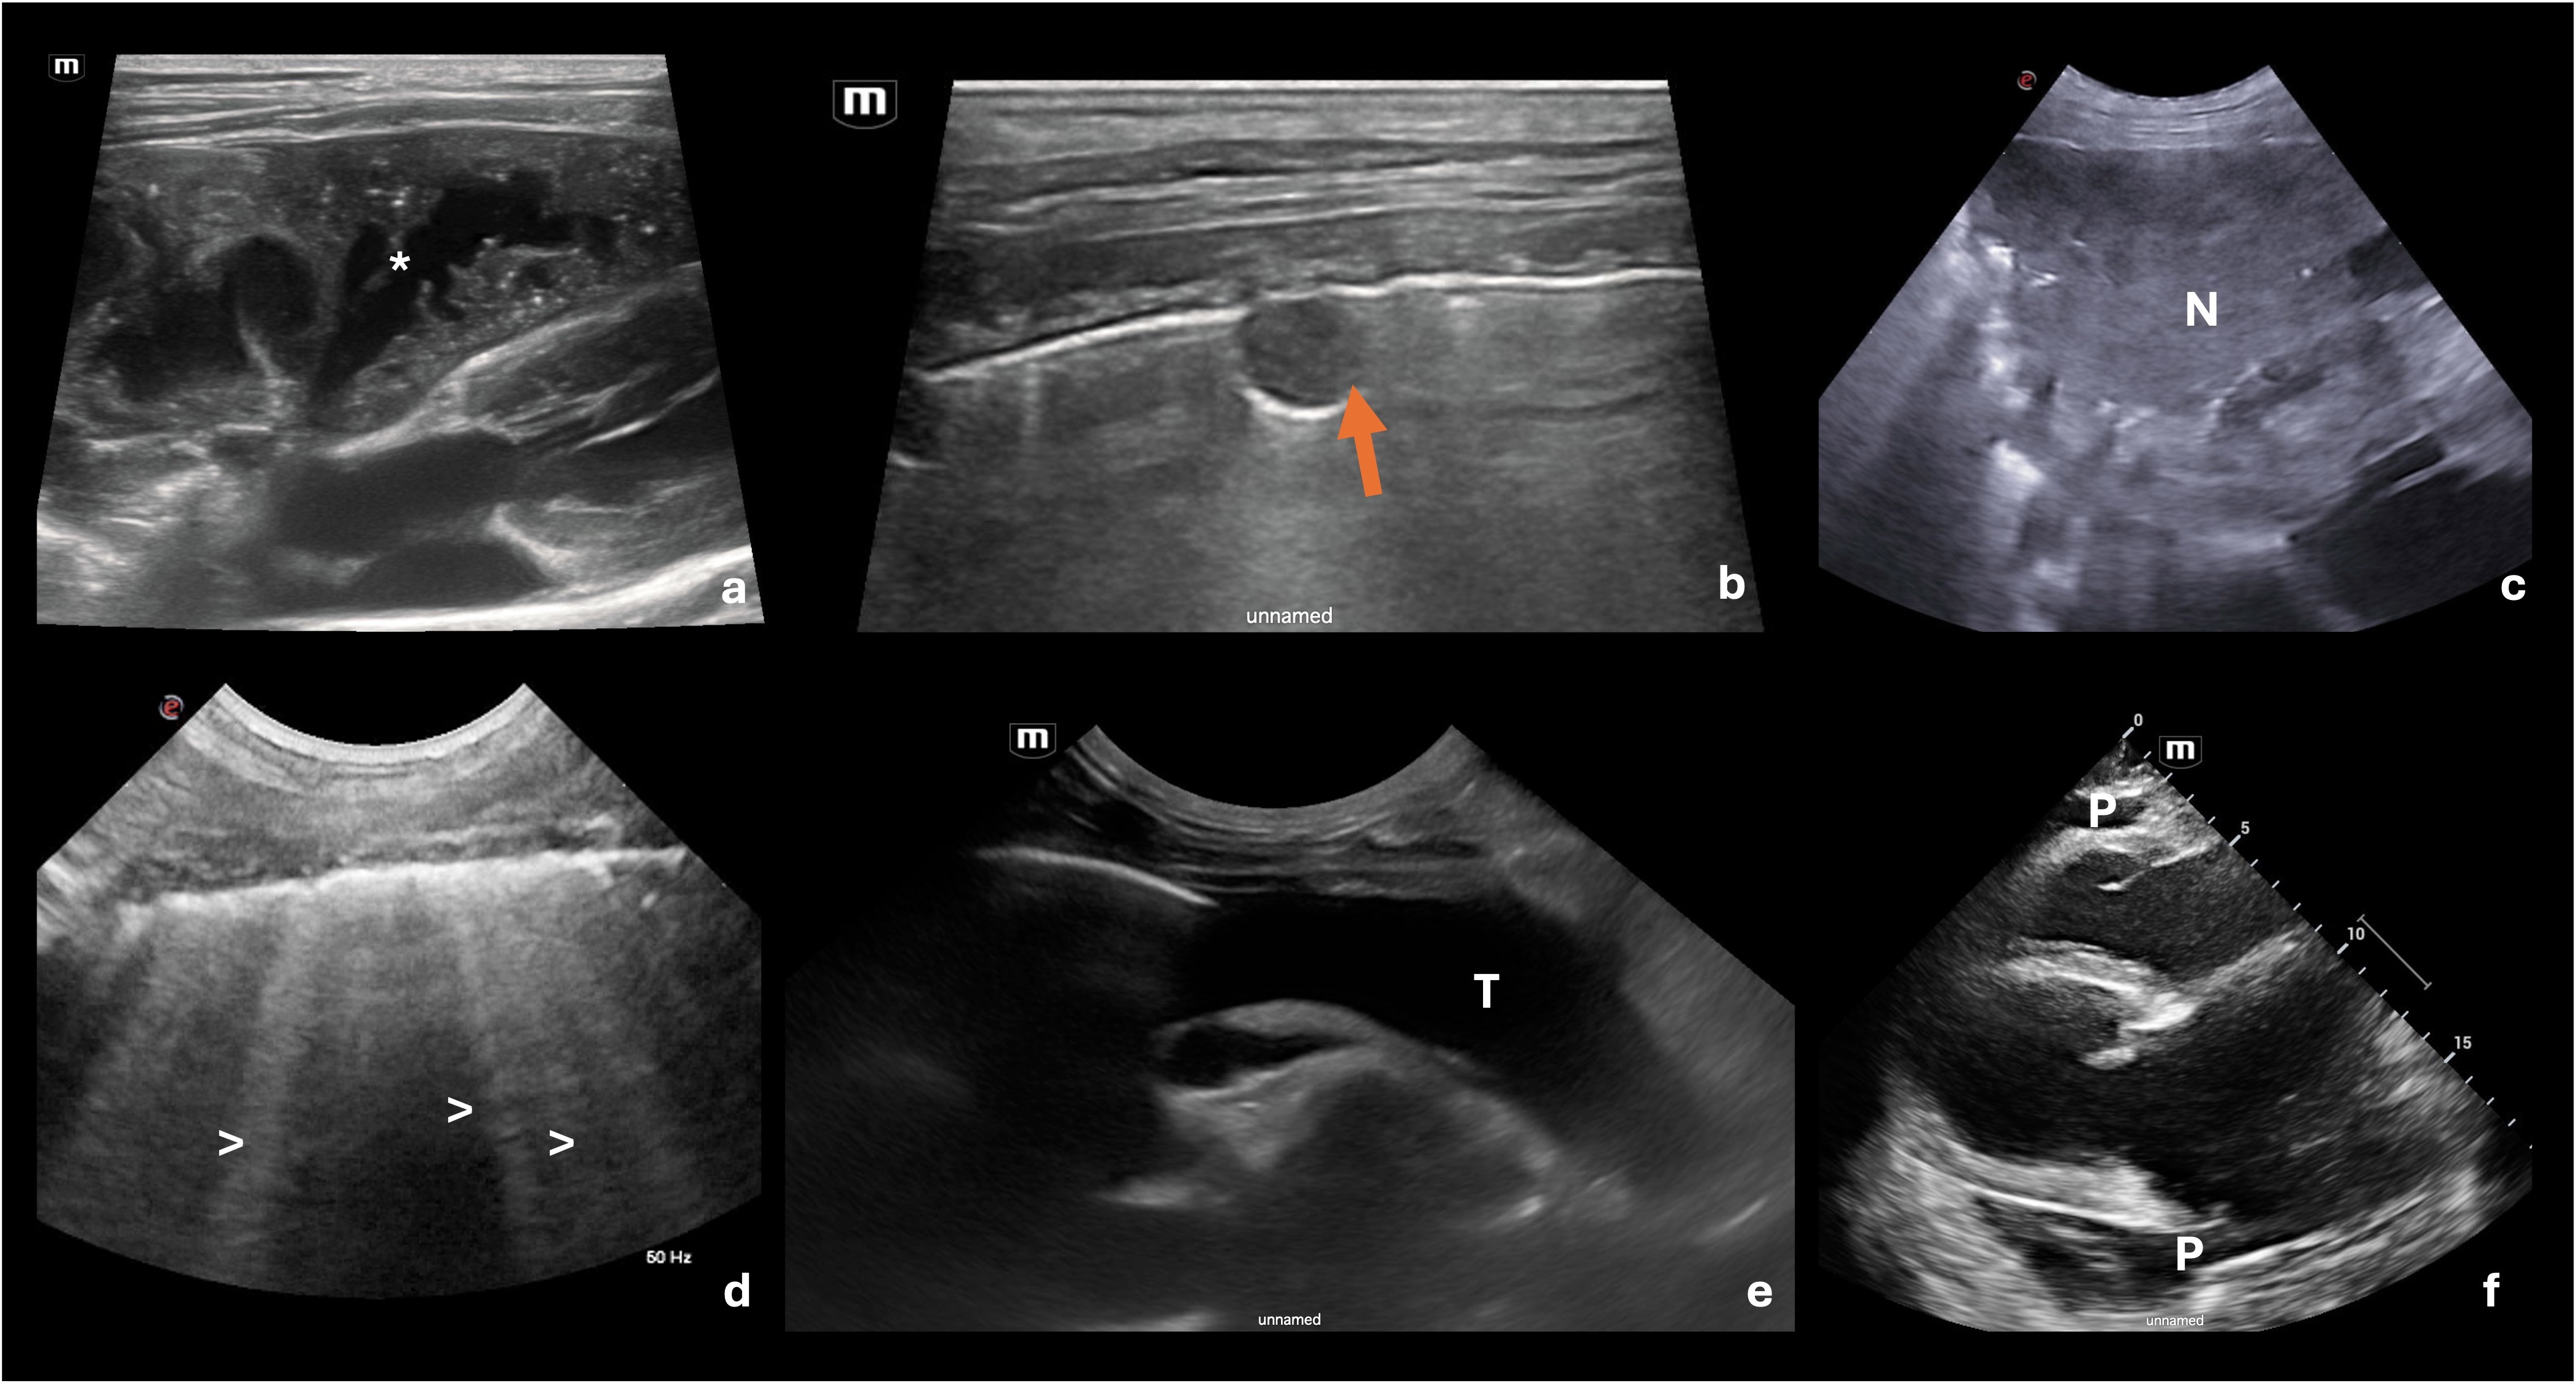

TFAST – thorakaler Ultraschall als Entscheidungshilfe im Notfall

Der thorakale Point-of-Care-Ultraschall, insbesondere im Rahmen des TFAST-Protokolls, ist ein etabliertes Instrument in der Notfall- und Intensivmedizin. Ziel ist nicht die vollständige Parenchymdiagnostik, sondern die rasche Beantwortung lebensentscheidender Fragen. Das Vorgehen ist prinzipiell auf Hund und Katze übertragbar - Abb. 3 zeigt die Durchführung bei einer Katze. In Abb. 4 werden verschiedene thorakale Ultraschallbefunde präsentiert. Neben dem TFAST hat der Ultraschall für die Probengewinnung eine große Bedeutung – ettliche pulmonale Läsionen lassen sich sonographisch darstellen und dann gezielt punktieren.

TFAST erlaubt eine hochsensitive Detektion von Pleuraergüssen, auch in sehr geringer Menge, und eignet sich hervorragend zur sicheren Punktionsplanung. Ebenso lassen sich Pneumothoraces zuverlässig erkennen, etwa durch fehlendes „lung sliding“ oder das Vorliegen eines „lung point“ (Grenze zwischen Pneumothorax und normaler Lunge). Perikardergüsse können zeitgleich beurteilt werden. Darüber hinaus sind pleuranahe Konsolidierungen sichtbar, etwa bei schweren Pneumonien oder Atelektasen. Zentrale oder milde parenchymale Veränderungen bleiben jedoch häufig unerkannt. TFAST ist daher klar als ergänzendes, frageorientiertes Verfahren zu verstehen und ersetzt weder Röntgen noch CT.

Verschiedene Ultraschallbefunde aus dem TFAST, ihre Ultraschallzeichen und die klinische Bedeutung sind in Tabelle 3 zusammengefasst.